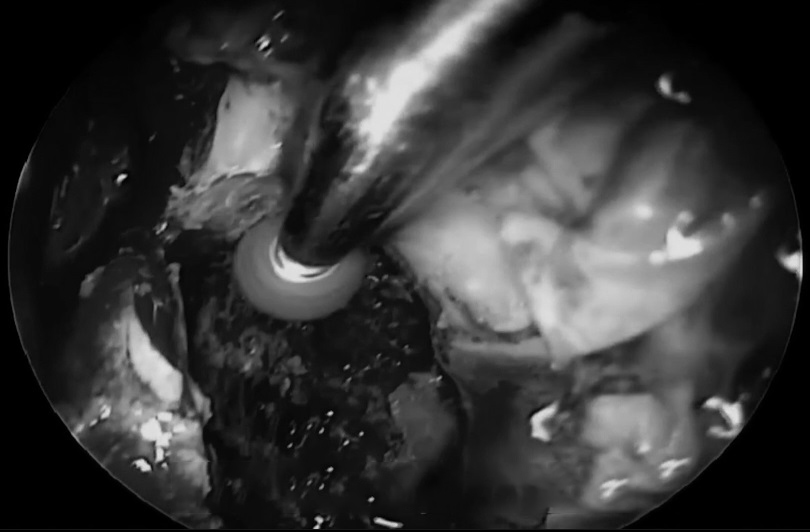

18kg,这么小体重患儿全身只有1500ml左右的血液含量,再一次手术难度较大,危险系数较高。手术中10%(150ml)的出血量,宁宁可能就会休克;出血量达到20%,就会危及生命。如何解决这个困境?福教授决定进行单鼻孔入路神经内镜手术,采用多种角度镜,运用“筷子技术”,用仅仅8mm的创口,切除了直径达50mm的肿瘤。在减少出血点的同时,将手术风险尽可能降到较低。

术中,年幼的宁宁鼻内空间很小,实行单鼻孔入路手术难度较大。福教授术后也直言道:“困难,像是打了很大的一场仗”。而此时距离一开始手术仅37天,幸运的是这次手术近全切肿瘤,宁宁术后3天转出ICU,无任何新增并发症。从远程咨询到成功手术仅10天,术后10天顺利出院。